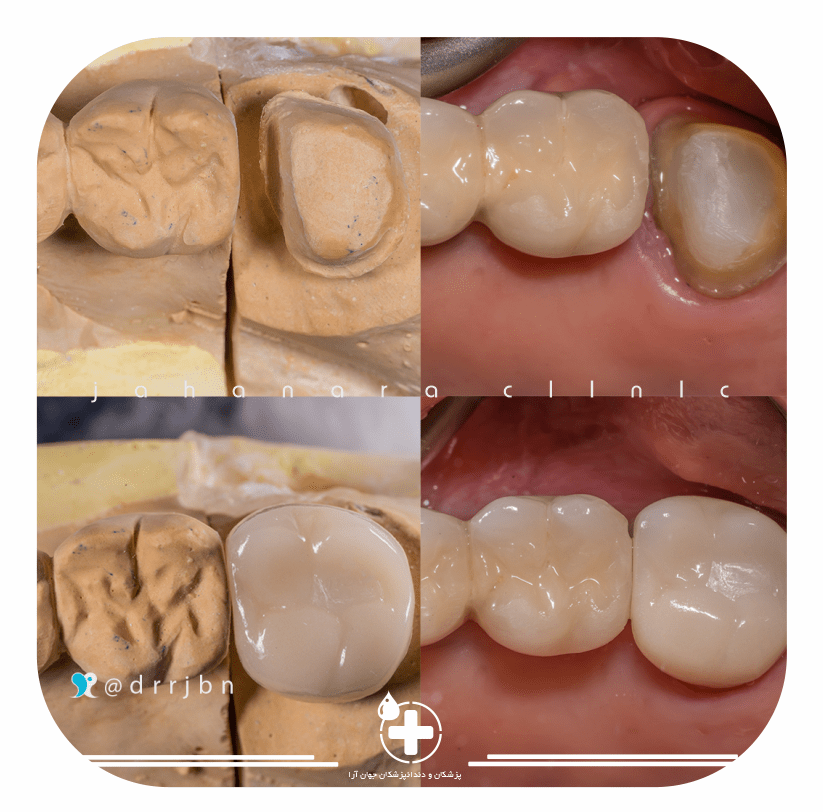

روکش و مصنوعی

روکش و دندان مصنوعیبا بهترین جنس و کیفیت